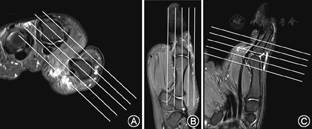

采用荷兰Philips Achieva 3.0 T超导MR扫描仪。线圈首选腕关节线圈SENSE-wrist-8,如果患者手大无法放入则改用中号柔线圈SENSE-Flex-M,扫描时患者俯卧于扫描床上,患肢伸直上举,五指并拢置于线圈中心,如使用柔线圈则需在手的掌侧及背侧放置薄海绵并用捆绑带固定。在前臂、腋下、胸部等位置放置海绵垫,病变的手指可采用支具外固定,并嘱咐其手指勿动,以避免产生伪影。根据临床病史,在病变部位粘贴标志,轴位扫描采用单一关节定位扫描(多关节病变时,多个关节分别定位,逐一进行轴位扫描)。矢状位和冠状位扫描采用以病变关节为中心,包括远近端相邻的两个关节,既有利于清晰显示病变部位,又可清晰显示韧带的附着点和韧带的纵向结构。此外,拇指扫描采用拇指外展位定位扫描,有利于显示内收肌腱膜和侧韧带的解剖结构,轴位扫描方法与其余四指相同,矢状位和冠状位分别采用与掌板垂直和平行扫描,即斜矢状位和斜冠状位扫描。视野(FOV)设置标准,第2~4手指轴位扫描,扫描野内应至少包括左右相邻的两个手指,矢状位和冠状位包括远近端各一个关节。拇指采用外展位扫描,轴位包括病变关节和内收肌远段,矢状位和冠状位包括远近端各一个关节。

患者取俯卧位,手指尽量伸直,线圈尽量裹紧关节,行轴位、冠状位、矢状位三个方位的质子压脂序列(PD-FS序列)扫描和冠状位T1WI序列扫描(图1,图2)。扫描参数:PD-FS序列,TE=40~45 ms,TR=3 000~4 000 ms,层厚2 mm,层间距0.2 mm,层数12层;冠状位FOV 140 mm×100 mm,矩阵348×244;矢状位FOV 140 mm×70 mm,矩阵348×210;轴位FOV 100 mm×100 mm,矩阵332×305。T1WI序列,TE=20 mm,TR=500 mm,层厚2 mm,层间距0.2 mm,层数12~24层;冠状位FOV 140 mm×100 mm,矩阵348×200;矢状位FOV 140 mm×70 mm,矩阵348×141;轴位FOV 100 mm×100 mm,矩阵332×285。

通常采用冠状位观察侧韧带的走行,轴位主要观察肌腱形态和覆盖于肌腱上相邻的支持带,以及是否有纵向撕裂或腱鞘积液[5] 。在临床上,最常见的手指侧韧带损伤为拇指掌指关节尺侧副韧带(UCL)损伤,MRI可以精确的根据有无内收肌腱膜的损伤将UCL损伤分为Stener损伤和非Stener损伤两型[6]。当发生伸肌腱和屈肌腱损伤时,通常采用矢状位和轴位观察。MRI可清楚显示矢状束、中央束、末端腱等手指伸肌结构以及伸肌腱和屈肌腱的损伤情况,尤其在急性期临床表现不典型时,矢状面为最佳检测平面[7]。文献报道,利用MRI图像与尸体解剖标本的对照,证实MRI对于伸、屈肌腱撕裂的诊断敏感性为92%,特异性为100%[8]。